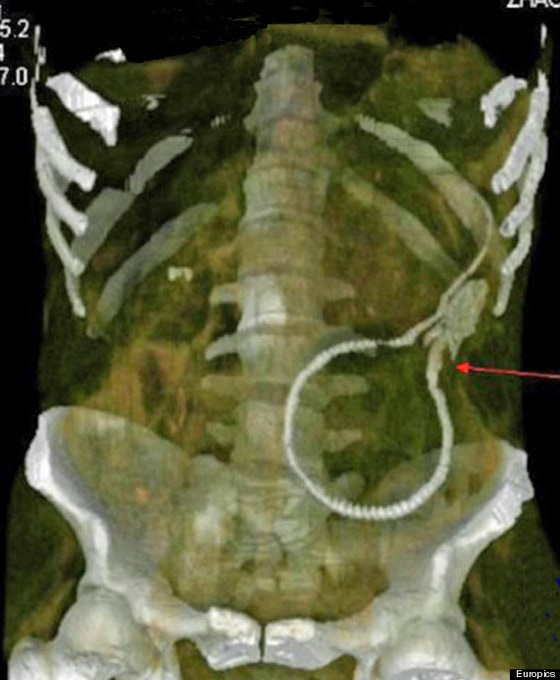

중국의 한 남성이 포르노 영화의 한 장면을 흉내내기 위해 항문을 통해 뱀장어를 몸 속에 밀어 넣었다가 응급실 신세를 졌다고 허핑턴포스트가 9일(현지시간) 보도했다.

중국 남동부 광둥성에 사는 이 남성은 포르노 영화를 본 뒤 뱀장어과 민물고기인 드렁허리(swamp eel)를 자신의 항문에 집어 넣었다.

갑작스레 어두컴컴한 사람 뱃 속에 갇힌 드렁허리는 나갈 길을 찾기 위해 몸부림쳤다. 이 과정에서 남성의 창자를 물어뜯어 구멍을 내는가 하면 내장 외벽에 달라붙기도 했다.

의료진은 대수술 끝에 드렁허리를 남성의 몸에서 꺼낼 수 있었다. 산 채로 다시 세상에 나온 드렁허리는 잠시 뒤 죽고 말았다.